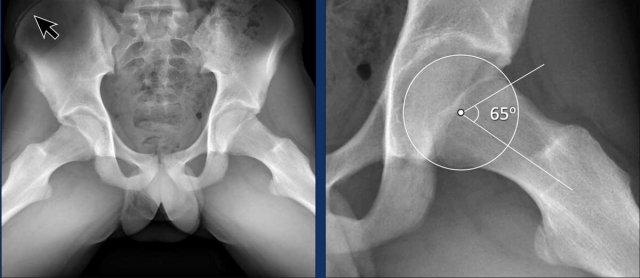

Đây là một trường hợp hình thái Cam khá tinh tế ở một nam giới trẻ tuổi.

Lưu ý rằng sụn tăng trưởng mào chậu chưa đóng lại (mũi tên).

Images

Two examples of Cam morphology.